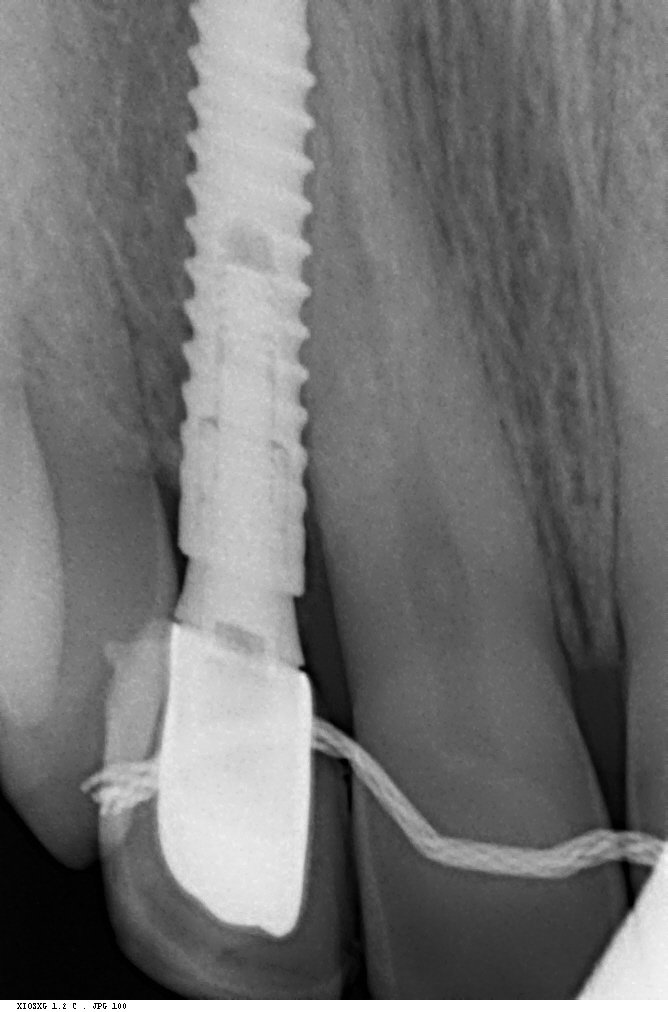

¿Qué implante es el de la posición 35?

Se trata de un caso con la corona cementada que presenta movilidad en boca, característica de que el tornillo del pilar está flojo y necesitaría saber la marca del implante [...]